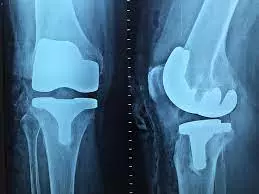

U ambulantnim uslovima izvodimo različite vrste intervencija - stopala i skočnog zgloba ruke, kolena, ramena i lakta.